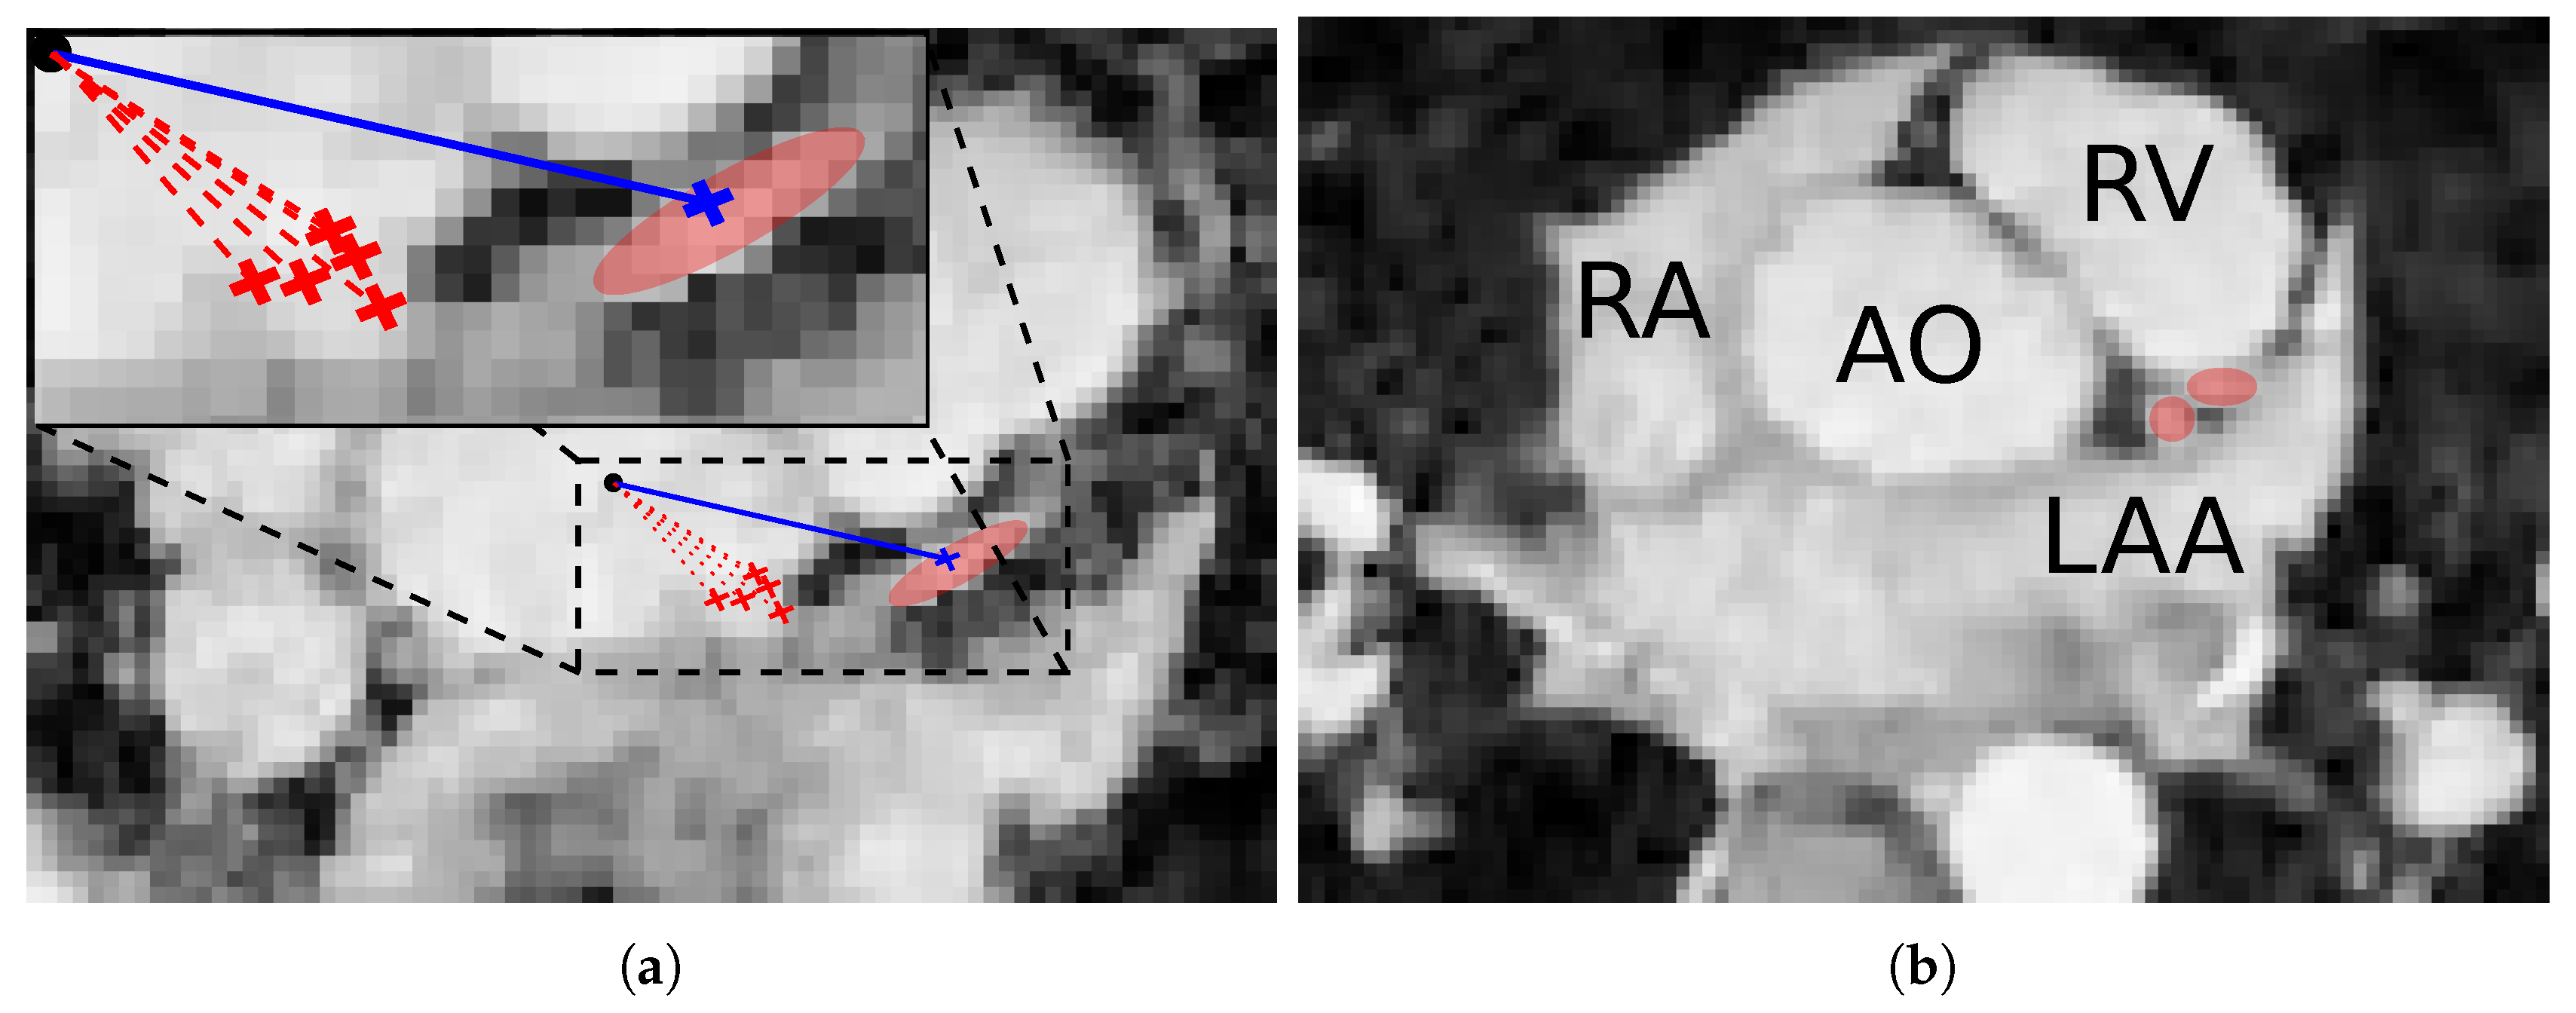

3.5. Ostia Detection

3.6. Coronary Centerline Extraction

5.1. Ostia Detection

6.2. Ostia Detection